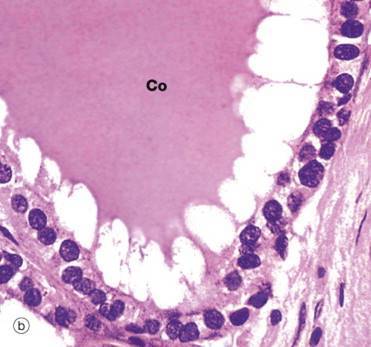

What cells are shown around the colloid structure?

Inactive Follicular epithelial cells of the thyroid